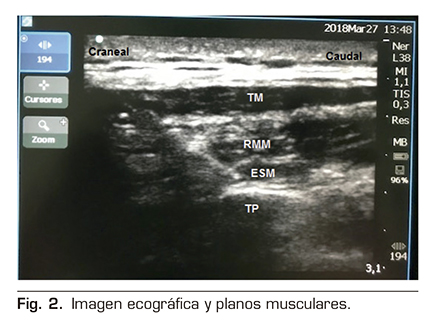

Figura 1